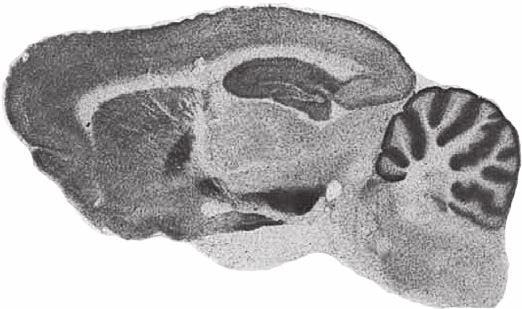

Сразу же стала очевидна параллель между этим экспериментом и наркозависимостью. В течение последующих десятилетий нейрофизиологическая цепь, выявленная Олдсом и Милнером, стала предметом тысяч исследований, в ходе которых удалось выяснить ее анатомические, химические и генетические составляющие, а также связь с поведением. Наиболее важное открытие заключается в том, что электрическая стимуляция, примененная в том первом эксперименте, приводила к выделению нейромедиатора дофамина в прилежащем ядре. Это зона в мозге, расположенная примерно в семи сантиметрах за нижним краем глазниц и относящаяся к лимбической системе – группе структур, отвечающих прежде всего за эмоции. Здесь дофамин выделялся нейронами в среднем мозге, идущими по мезолимбическому пути (из названия понятно, что путь пролегает из среднего мозга (греч. meso-), в лимбическую систему).

Мезолимбический путь